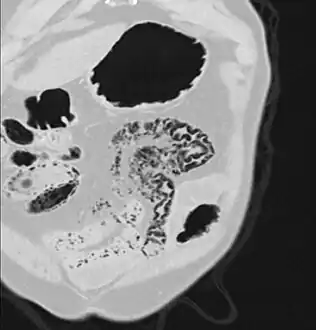

Coronal reformatted MDCT image showing extensive pneumatosis intestinalis in the left upper quadrant small bowel. The pneumatosis is more cystic and nodular in the small bowel in the midline and the right of midline. This patient had a relatively benign presentation without bowel ischemia and was treated conservatively.